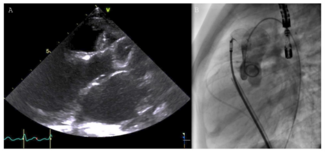

Dawei Lin, MD1,2; Shasha Chen, MD1,2; Daxin Zhou, MD1,2; Wenzhi Pan, MD1,2; Junbo Ge, MD1,2

A 76-year-old man diagnosed with severe pure native aortic regurgitation underwent transcatheter aortic valve replacement due to high surgical risk. The computed tomography angiography showed no calcification and no stenosis of the aortic...

Abhinav Jain, MD1; Sourabh Agstam, MD, DM, MRCP(UK), FACC1; Mayank Yadav, MS, MCH2; Sivasubramanian Ramakrishnan, MD, DM, FACC1; Rakesh Yadav, MD, DM1

Abhinav Jain, MD1; Sourabh Agstam, MD...

A 16-year-old girl was referred to our tertiary care center for management of a failed aortic valve balloon dilatation procedure for congenital valvular aortic stenosis .